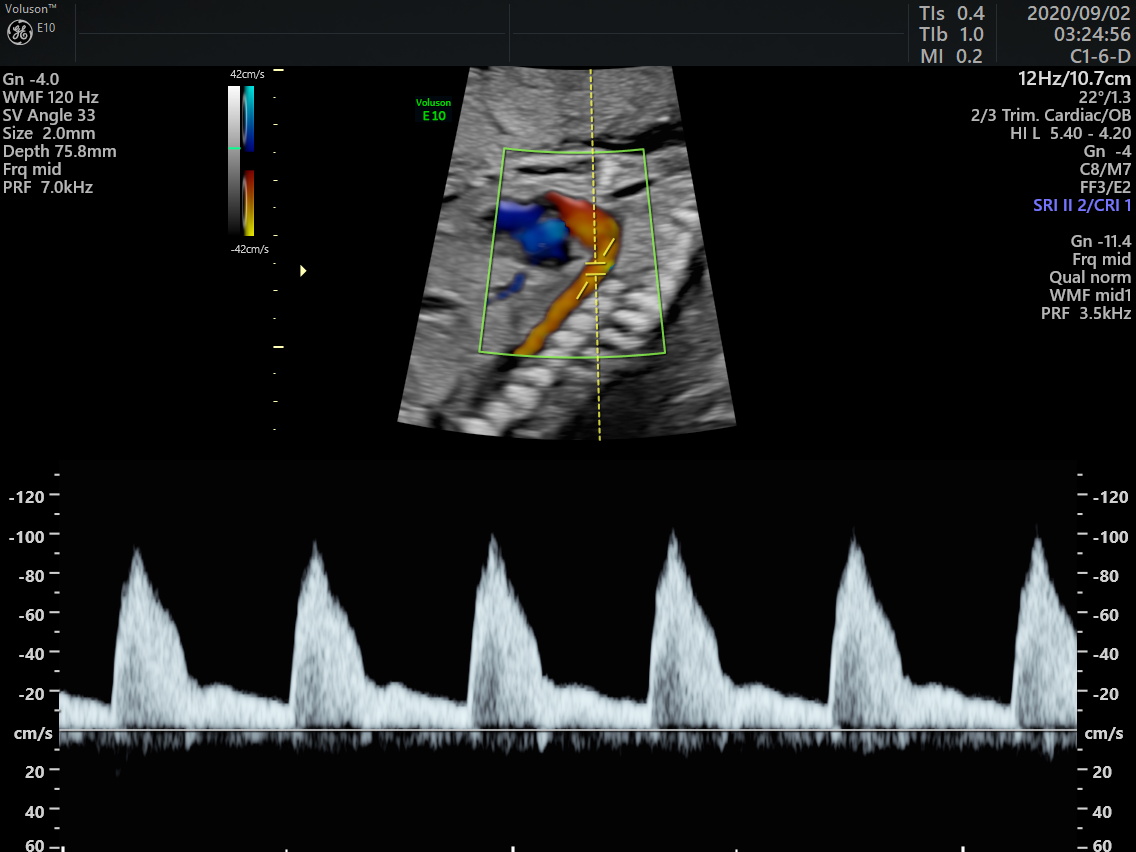

胎児診療では超音波検査による胎児の診察と、羊水検査に代表される遺伝学的検査も行なっています。

クアトロ検査を希望の方へは遺伝カウンセリングを行っています。また、FMF精密胎児超音波ドックを受けていただき、その後採血検査を行います。